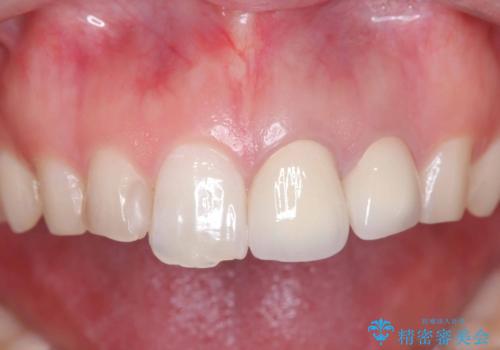

治療内容:

左上2番に対して精密根管治療を実施し、感染源の除去を行いました。その後、左上1、2番ともにオールセラミッククラウンによる補綴を行い、審美的な修復を行いました。

治療結果:

痛みは消失し、患者様の審美的な満足度も高く、良好な治療結果が得られました。